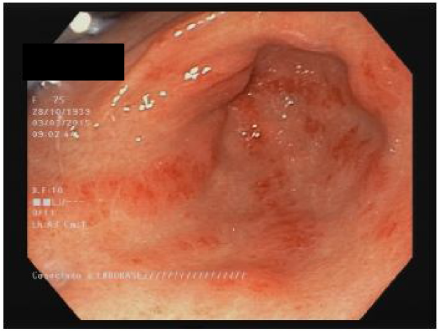

Alrededor del 50% de los pacientes con ES tienen compromiso estomacal13,60. Las manifestaciones más frecuentes son el retardo en el vaciamiento gástrico y la ectasia vascular antral gástrica (EVAG o estómago en sandía; fig. 1)8,10,88. Aunque se desconoce el mecanismo específico de la enfermedad gástrica, se han propuesto como posibles causas el dano microvascular, un compromiso del sistema nervioso periférico y la disfunción miogénica41. La gastroparesia puede afectar al 10-80% de los pacientes3,8,14,48,61,89,90.

La EVAG se encuentra hasta en 22,3% de los pacientes88. La EVAG probablemente se produce debido a una alteración del componente microvascular de la ES8,101. Un estudio reciente encontró una mayor presencia de EVA Genlospacientes con diagnóstico temprano de ES y en los pacientes del subgrupo difuso (ESdc)10. También se publicó una asociación negativa con anticuerpos antitopoisomerasa (ATA)102 y anti-U1-ribonucleoproteina88. La asociación de la EVAG con otros autoanticuerpos es objeto de controversia103. Las principales manifestaciones clínicas incluyen anemia por deficiencia de hierro o hemorragia gastrointestinal alta103. Cabe señalar la recomendación de descartar la presencia de ES en los pacientes con EVAG88,101. El diagnóstico se hace por endoscopia, que muestra múltiples ectasias vasculares pequenas confluentes con orientación longitudinal desde los pliegues del antro hasta el píloro104. El tratamiento inicial es una terapia de apoyo con suplementos de hierro o transfusiones de glóbulos rojos. Si la terapia conservadora falla, se requerirá terapia endoscópica con ablación laser, fotocoagulación con argón plasma o ligadura endoscópica con banda, especialmente para los pacientes con sangrado relacionado con EVAG44. La antrectomía está reservada únicamente para los casos graves105.